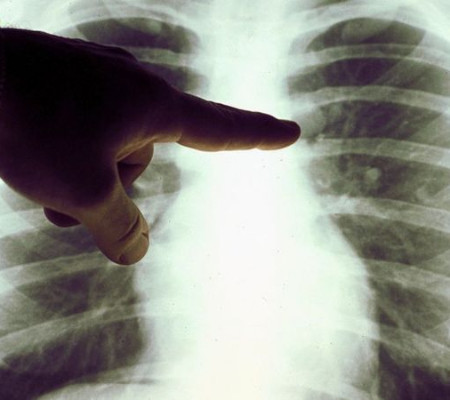

Caso de linfoma | Foto: Reprodução